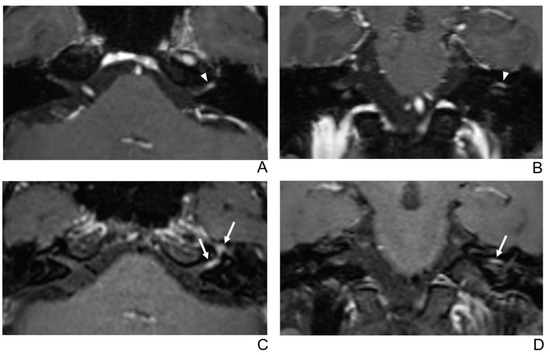

Figure 4.

A 56-year-old female patient with right facial neuritis. (A–D) Paired axial and coronal CE-GRE (A,B) and T1 BB-FSE (C,D) images of the same patient. In the axial (A) and coronal (B) CE-GRE images, no definite asymmetric enhancement was demonstrated in the bilateral facial nerves (arrowheads); thus, it was evaluated by reviewers 1 and 2 as normal facial nerves (false negative). In contrast, the right facial nerve shows asymmetric intense enhancement in the canalicular, labyrinthine, and anterior genu segments in the T1 BB-FSE axial (C) and coronal (D) images (arrows); thus, the two reviewers interpreted the enhancement as right facial neuritis (true positive; 2, diagnostic confidence; 3, 2, and 3, visual grades for CE in the canalicular, labyrinthine, and anterior genu segments, respectively).